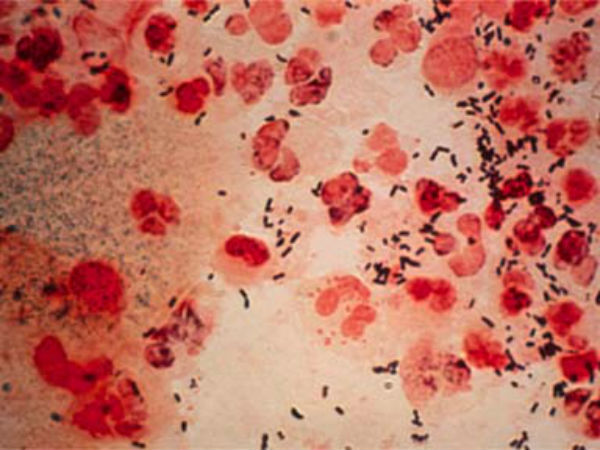

ലണ്ടന്: യൂറോപ്പിനെ ഞെട്ടിച്ച് ലൈഗിക രോഗമായ സിഫീലിസ് വ്യാപിക്കുന്നതായി റിപ്പോര്ട്ട്. നിരവധി നീലച്ചിത്ര അഭിനേതാക്കള്ക്ക് രോഗം സ്ഥിരീകരിച്ചെന്നും ഒട്ടേറെ പേര് അഭിനയം നിര്ത്തിയെന്ന റിപ്പോര്ട്ടും പുറത്തുവരുന്നുണ്ട്. ലൈംഗിക സമ്പര്ക്കത്തിലൂടെയാണ് സിഫിലിസ് പകരുന്നത്, ചര്മ്മത്തില് മുറിവുകള്ക്കും ചുണങ്ങുകള്ക്കും കാരണമാകുന്നു. അമേരിക്കയിലെ നീലച്ചിത്ര അഭിനേതാക്കളുടെ സെക്ഷ്യല് ഹെല്ത്ത് സര്ട്ടിഫിക്കറ്റുകളുടെ ഡാറ്റബേസ് സൂക്ഷിക്കുന്ന പാസ് ആണ് ഇത് സംബന്ധിച്ച റിപ്പോര്ട്ട് പുറത്തിവിട്ടത്.

മികച്ച താരങ്ങള് ഇപ്പോള് കടുത്ത ആശങ്കയിലാണെന്ന് അവര് വ്യക്തമാക്കുന്നു. അവരുടെ വരുമാന മാര്ഗം ഇപ്പോള് നഷ്ടപ്പെട്ടിരിക്കുകയാണെന്നും താരം വ്യക്തമാക്കുന്നു. വെറും ഒരു ചര്മ്മ രോഗം മാത്രമല്ലിത്. സിഫിലിസിന്റെ ആദ്യ ലക്ഷണം ഒരു ചെറിയ വ്രണമാണെന്നാണ് ആരോഗ്യവിദഗ്ദര് പറയുന്നത്.

സിഫിലിസ് ഘട്ടങ്ങളില് വികസിക്കുകയാണ് ചെയ്യാറുള്ളത്. ഓരോ ഘട്ടത്തിലും ലക്ഷണങ്ങള് വ്യത്യാസപ്പെടുന്നു. വര്ഷങ്ങളോളം രോഗലക്ഷണങ്ങളൊന്നും കാണാതെ നിങ്ങള്ക്ക് സിഫിലിസ് ബാധിച്ചേക്കാം. ബാക്ടീരിയ നിങ്ങളുടെ ശരീരത്തില് പ്രവേശിച്ച സ്ഥലത്താണ് വ്രണം പ്രത്യക്ഷപ്പെടുന്നതെന്നാണ് ആരോഗ്യ വിദഗ്ദർ വ്യക്തമാക്കുന്നത്.

സിഫിലിസ് ചാന്സറുകളുമായോ വ്രണങ്ങളുമായോ നേരിട്ടുള്ള സമ്പര്ക്കത്തിലൂടെയാണ് സിഫിലിസ് പകരുന്നത്. ഈ വ്രണങ്ങള് വികസിക്കുന്നതിന് പ്രവണതയുണ്ട്. സിഫിലിസ് പ്രാഥമികമായി ലൈംഗികമായി പകരുന്നത്. ലൈംഗികതയിലൂടെയോ അല്ലെങ്കില് നേരിട്ട് ജനനേന്ദ്രിയത്തില് നിന്ന് ജനനേന്ദ്രിയത്തിലേക്കുള്ള സമ്പര്ക്കത്തിലൂടെയോ പകരാം.